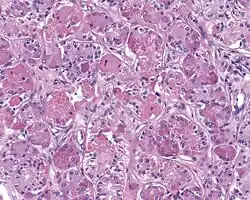

High power H&E stained image of a parotid sclerosing polycystic adenoma with eosinophilic granules

When reviewed by a pathologist, the findings are quite similar to fibrocystic changes of the breast, although they are different enough, that it is now recognized to actually represent a true neoplasm (clonal proliferation) through various studies.[5] Specifically, the lesions are usually well-circumscribed, containing lobules of haphazardly arranged ducts, myoepithelial cells, and acini that have abundant sclerosing or hyalinized fibrosis. Apocrine change is quite common in the ductal cells.[6] The ducts range from small ductules to cystically dilated spaces (more than 4 striated duct-widths across), often containing products of secretion or reactive histiocytes. A very curious and characteristic finding in all of the lesions is the presence of bright pink (eosinophilic) acinar granules (which are altered zymogen).